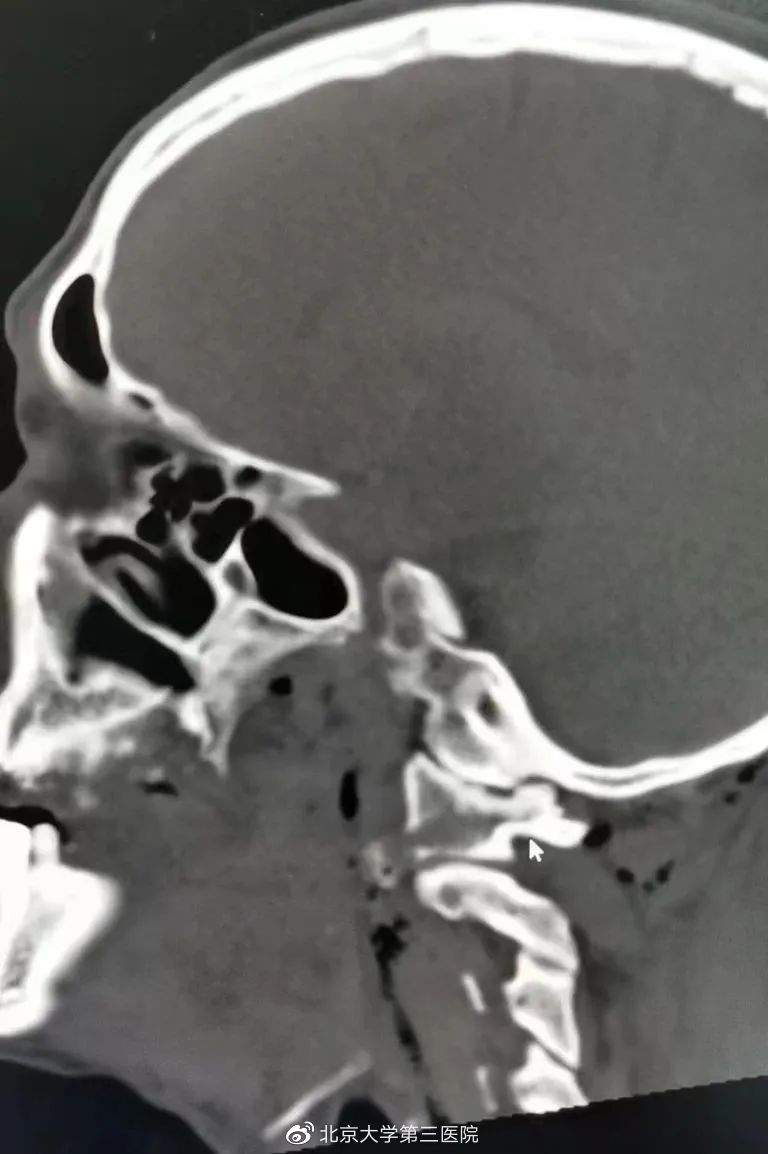

图 | CT结果显示寰椎骨折

CT结果显示,患者口腔中多个牙齿断裂及左侧寰椎侧块骨折,异物位于左颈后,部分穿出体外。